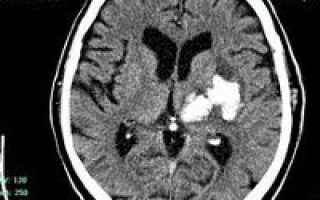

• КТ головного мозга. На томограммах внутримозговая гематома выглядит как очаг гомогенной плотности округлой или овальной формы. Если гематома возникла из-за ушиба головного мозга, она обычно имеет неровные контуры. Со временем плотность гематомы уменьшается до изоплотного состояния, соответствующего плотности мозговой ткани. Для малых гематом этот процесс занимает 2-3 недели, для средних — до 5 недель.

В диагностике нейровизуализация играет важную роль. Первоначально для исследования головного мозга назначают компьютерную томографию (КТ). Этот доступный метод позволяет быстро определить наличие крови в веществе головного мозга, а также расположение и объем сгустка. Информативность КТ максимальна через 2-3 недели после появления гематомы (максимум 5 недель). В этот период участок внутримозговой гематомы (ВМГ) имеет повышенную плотность, что облегчает диагностику, и можно ограничиться одной КТ.

С течением времени (в среднем через 14-21 день) плотность геморрагической массы уменьшается, и она становится изоплотной, то есть приближается к плотности нормальных мозговых тканей. В этот период и позже качественные данные о внутримозговой гематоме и состоянии мозга может предоставить магнитно-резонансная томография (МРТ).